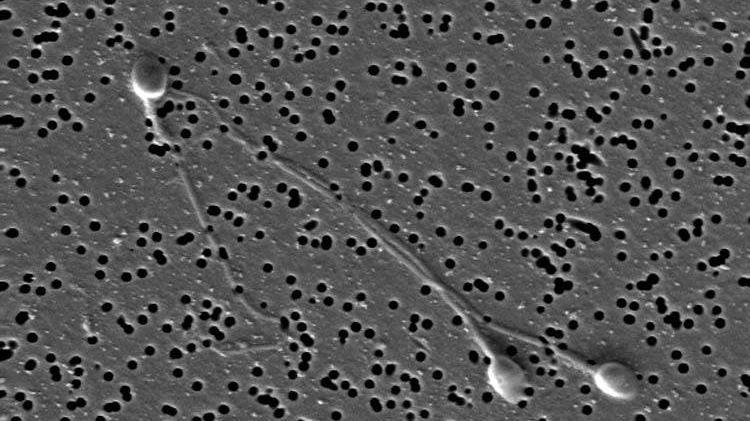

El resultado fue alcanzado por dos estudios realizados en ratones por un equipo internacional de investigadores. Concretamente, en la primera investigación se fertilizaron óvulos de ratón utilizando esperma de un grupo de roedores que habían sido alimentados con una dieta rica en grasas y de otro que había seguido una dieta normal.

En este sentido, y con el objetivo de conocer si el ARN del esperma era el responsable de estas diferencias entre las crías de los padres que se habían alimentado con una dieta rica en grasas y los que habían consumido una dieta normal, los expertos purificaron el ARN de ambos grupos y los inyectaron en cigotos normales.

Una vez realizado, los investigadores comprobaron que el ARN de esperma de los machos que habían consumido mucha grasa contenía la información necesaria para provocar a sus crías intolerancia a la glucosa, aunque no resistencia a la insulina, según publica la revista Science.

En un segundo estudio, los científicos comprobaron si el esperma de los ratones en una dieta baja en proteínas (LP) manifestaba algún cambio en los niveles de ARN. Así, mostraron que los ARN pequeños de esperma inmaduro en los testículos no habían estado relacionados con efectos dietéticos, aunque la secuenciación del ARN pequeño en el esperma maduro del epidídimo reveló un aumento de la regulación de ciertos ARN.

A continuación, el equipo aisló el ARN en el esperma de ratones LP y ratones del grupo de control, y descubrió niveles particularmente altos de un ARN (el ARNt-Gly-GCC), en el grupo LP. Finalmente, un posterior análisis desveló que el ARNt-Gly-GCC suprime un subconjunto de genes, incluyendo el retroelemento MERVL.

Por tanto, los resultados de ambos trabajos han desvelado cómo el ARN del esperma puede verse afectado por la dieta, y han alertado de que este hecho puede ocasionar cambios en la regulación genética de la descendencia y el trastorno.